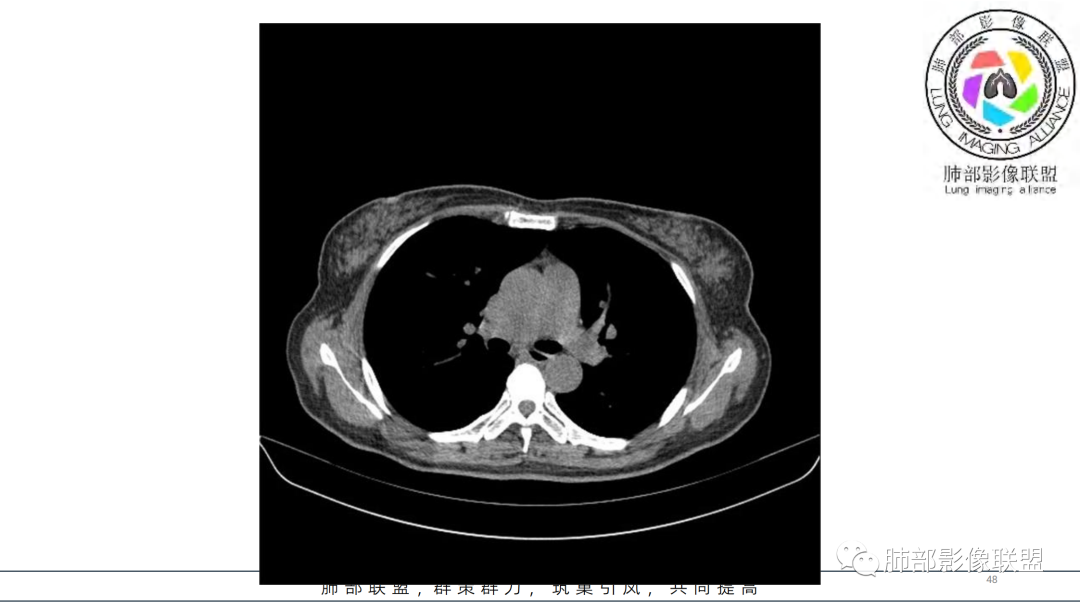

2.右肺下叶及中间段支气管后方类圆形块影,边界较清楚,未见分叶及毛刺,病灶部分突入支气管腔内(冰山一角),局部管腔狭窄,相应肺叶未见片影或体积变化。

3.块影密度均匀,未见液化坏死及钙化,渐进性强化,强化显著。

中青年女性,支气管管腔内外肿块(“冰山征”),边界较清楚,强化显著,未见阻塞性肺不张,尽管未出现“类癌综合征”临床表现,仍然符合典型类癌影像学表现。